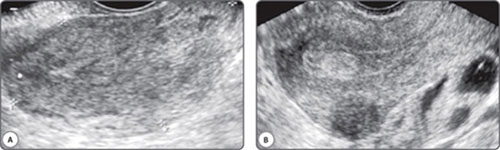

The vast majority of scans in fertility patients are transvaginal scans. Since the transducer is closer to the region of interest than with transabdominal scans, a higher transducer frequency can be used. This greatly enhances resolution. Currently available transducers employ frequencies of up to 12 MHz, and the difference in resolution is remarkable (Figs 1A and B). The trade-off with higher frequencies is of course, depth penetration of the beam, and these higher frequency transducers have a limited resolution beyond a certain distance from the transducer. This limitation can be overcome by using a multifrequency transducer. Console keys permit a choice of low, middle and high frequencies with the same transducer, enabling a great combination of resolution and depth. Transabdominal transducers have an advantage of a more panoramic field of view and a greater depth of penetration. These are therefore useful for identifying extraovarian adnexal structures and ovaries located at the pelvic brim. They are also indispensable for the assessment of associated abdominal lymph node disease, the suprarenal glands, kidneys, liver, abdominal peritoneal disease and the pleura.

Figs 1A and B: Images from the same patient using a (A) 5 Mhz and a (B) 12 Mhz transducer frequency. The inhomogeneous endometrium translates into an echogenic polyp. The indistinct posterior uterine wall on a higher frequency reveals an intramural fibroid. Thick-walled fluid loculi are evident posterior to the uterus on a high frequency study